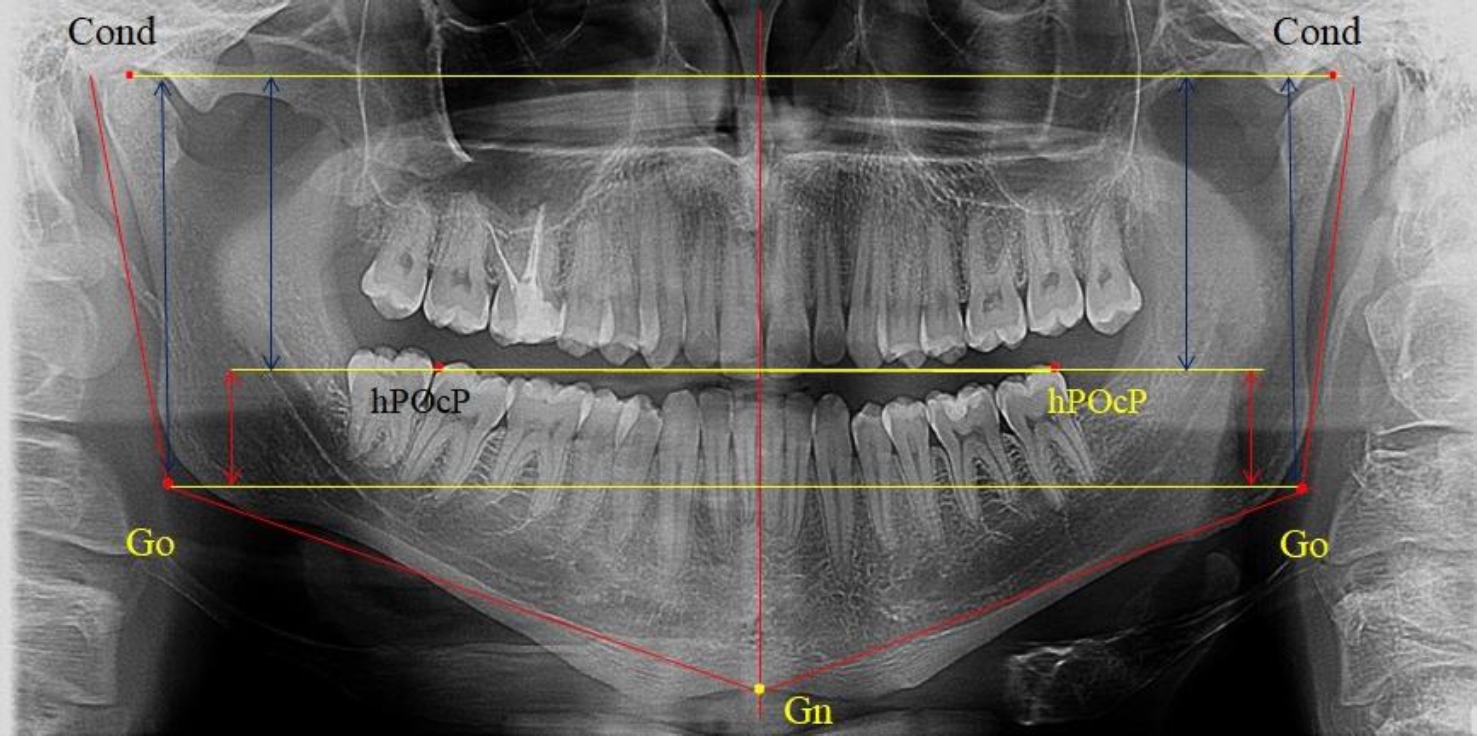

На боковых телерентгенограммах определяли положение верхней точки суставной головки Cond. Касательные линии к ветви и телу нижней челюсти пересекались в точке, которую в клинической практике обозначают как точка угла нижней челюсти или точка гонион Go. Точкой hPOcP обозначали дистальный бугорок нижнего второго моляра вблизи окклюзионного контура коронки, через нее от межрезцовой точки проводили окклюзионную линию, ее продолжали до задней части ветви челюсти. Высоту ветви измеряли как расстояние от угла нижней челюсти до вершины суставной головки Go-Cond. Общую высоту ветви условно делили на 2 части, ее границей служила окклюзионная линия. Верхнюю часть обозначали как окклюзионно-суставная, а нижнюю – как окклюзионно-гониональная.

На ортопантомограмме использовали аналогичные суставные точки Cond на каждой стороне, их соединяли между собой суставной линией Cond-Cond.

Касательная к ветви нижней челюсти соединяла выступающие точку. При построении касательной к телу челюсти проводили в обе стороны линии от точки Gn, расположенной в нижней центральной части подбородочного симфиза, до выступающей нижней точки угла челюсти. Касательные линии при пересечении определяли конструктивную точку гонион Go. Соединение гониональных точек определяло положение гониональной линии Go-Go. При соединении окклюзионных точек hPOcP получали окклюзионную горизонталь (рис. 1). Измеряли расстояние между горизонталями в области ветвей нижней челюсти. Статистический анализ проводили в программе Microsoft Excel. Составляли вариационные ряды с последующим расчетом среднего значения, стандартного отклонения и ошибки среднего ±m. Также оценивали максимальные и минимальные значения величин. Определи относительные величины соотношения верхней и нижней частей ветви нижней челюсти.

Рис. 1. Метод измерения высоты ветви нижней челюсти на телерентгенограмме (а) и ортопантомограмме (б)